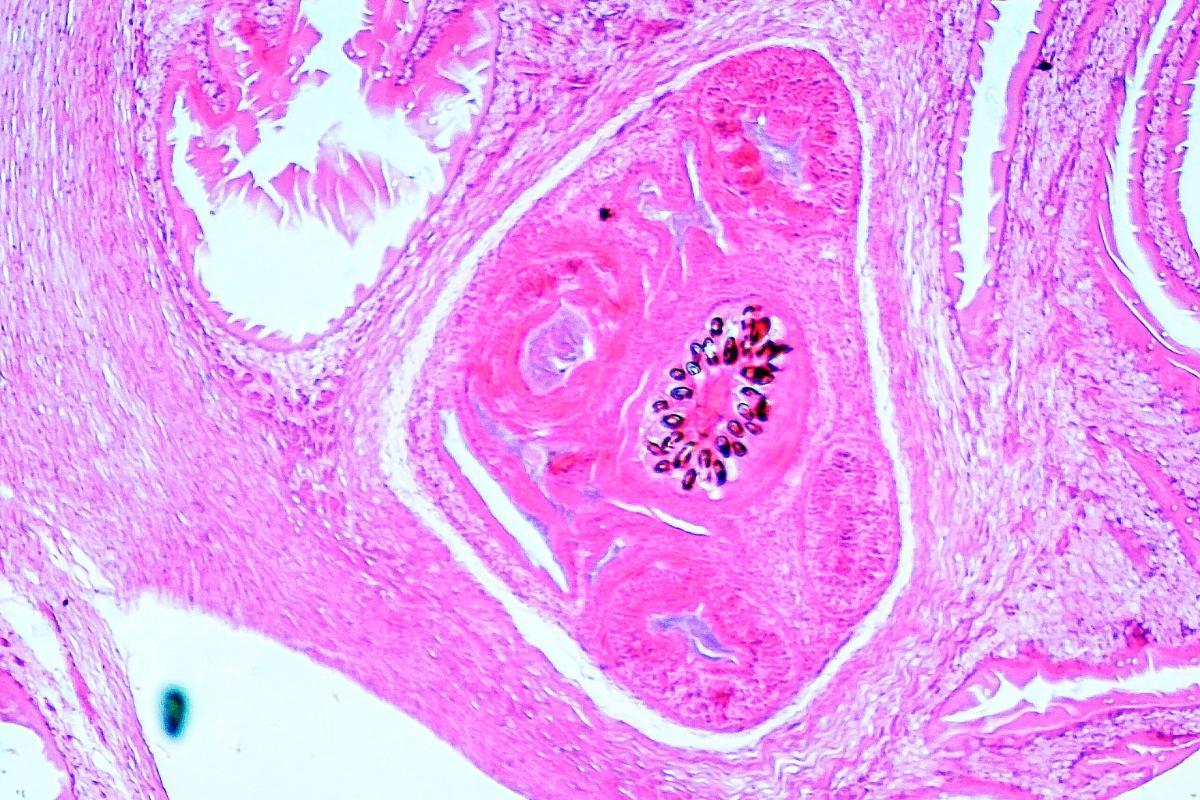

Esse tipo de parasita se caracteriza por liberar os ovos através das fezes, que são visíveis macroscopicamente como grãos de arroz, e por interferir na absorção de nutrientes do hospedeiro, enfraquecendo-o gradualmente. Embora coma e tenha apetite, o cachorro afetado perde peso por não conseguir absorver os nutrientes. A principal tênia que se transmite por essa via através dos cães é Echinococcus granulosus, causadora do cisto hidático em humanos.

O ser humano atua como hospedeiro intermediário enquanto o cão é o hospedeiro definitivo, já que a tênia evolui até seu estado adulto localizado no intestino canino. No caso dos humanos, os ovos evoluem para larvas que não se alojam no intestino, mas a partir daí migram através das veias mesentéricas ou dos vasos linfáticos, sendo levadas pelo sistema circulatório a qualquer parte do organismo, desenvolvendo-se principalmente no fígado em 65-75% dos casos após chegarem pela veia porta.

Se a hipótese anterior não ocorrer, tais parasitas se dirigirem pelas veias supra-hepáticas, pela veia cava inferior, chegando ao coração direito e posteriormente saindo pela artéria pulmonar, alcançam o pulmão em até 30% dos casos. Se evitarem essas duas principais localizações e, pela circulação sanguínea, chegarem a qualquer outro órgão como o rim, o peritônio, o cérebro ou os ossos, também ocorre o cisto hidático. O crescimento deste pode causar sintomas dependendo da localização, como sangramentos, compressão vascular, atrofias, hipertensão craniana, icterícia, insuficiência hepática, doenças pulmonares ou sintomas neurológicos, entre outros.